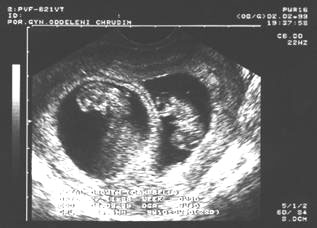

9. týden: plodové vejce

9.týden